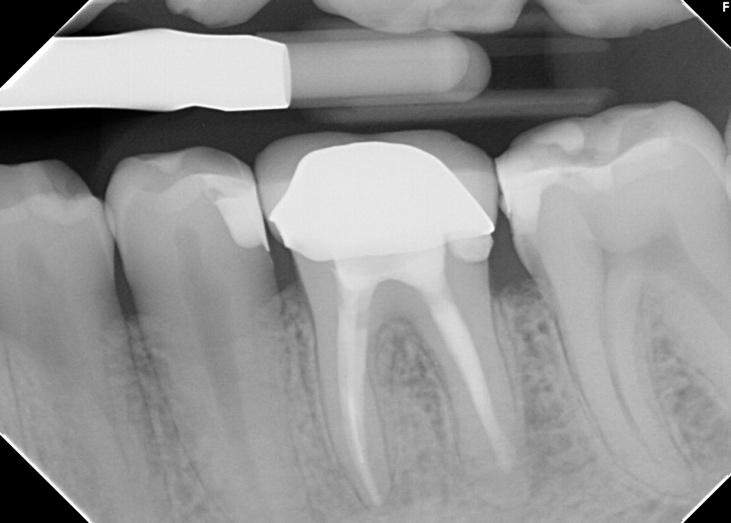

Fig 3. Single-cone hydraulic technique using EdgeBioCeramic Sealer (EdgeEndo) was performed. The selection of this method aimed to streamline cone fitting processes within intricate anatomical structures, as the sealer, rather than gutta-percha, is responsible for establishing the apical hermetic seal. The gutta-percha cone only acts as a carrier and there is no need to get a proper tugback, which would be difficult to achieve in such complex anatomy. The favorable handling properties and flowability of the EdgeBioCeramic Sealer allowed easy root canal obturation procedure.

Case 2: A 52-year-old female referred to the clinic for the treatment of tooth 21. Intra-oral examination showed a poor restoration on tooth 21. Percussion and palpation were negative with mobility grade 1. Radiographic examination showed an unsatisfactory restauration on tooth 21 with an apical radiolucency. After obtaining the written consent, the treatment was carried out. The area was anesthetized. Tooth was isolated using the rubber dam and access cavity was opened. The root canal used for shaping was the EdgeTaper Blaze Utopia to size F2 #25. The final irrigation protocol was performed by a continuous delivery of EDTA and NaOCl. Solutions were activated using ultrasonic activation - 1 minute per solution. Canals were dried and obturated using hydraulic condensation with EdgeBioCeramic Sealer (EdgeEndo). Lateral and secondary canals are visible on the post operative radiograph.

Case 2: A 36-year-old female referred to the clinic for the treatment of tooth #46. Intra-oral examination showed a deep caries lesion on tooth #46. The tooth was Percussion tender and lingering to cold testing. Radiographic examination revealed a deep caries. The area was anesthetized. Tooth was isolated using the rubber dam and access cavity was opened. The root canal used for shaping was the EdgeEndo Utopia X7 to size 30.04 in the mesials and 35.04 in the distal canal. The final irrigation protocol was performed by a continuous delivery of EDTA and NaOCl. Solutions were activated using ultrasonic activation - 1 minute per solution. Canals were dried and obturated using hydraulic condensation with EdgeBioCeramic Sealer (EdgeEndo).